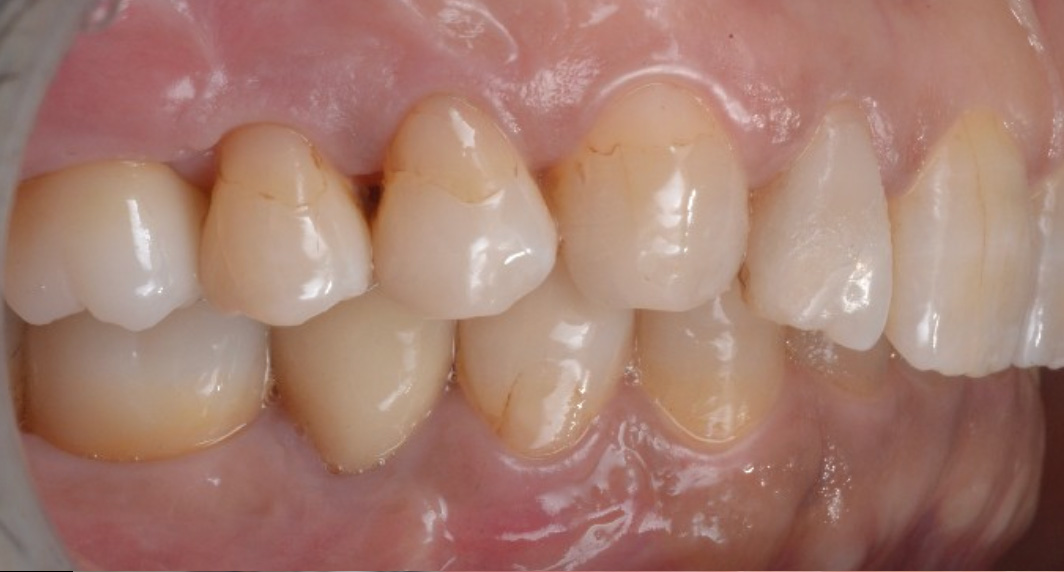

治療後